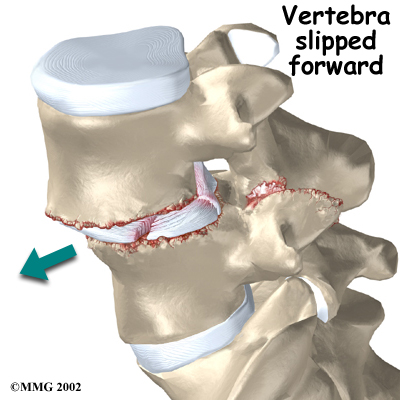

Normally, the bones of the spine (the vertebrae) stand neatly stacked on top of one another. Ligaments and joints support the spine. Spondylolisthesis alters the alignment of the spine. In this condition, one of the spine bones slips forward over the one below it. As the bone slips forward, the nearby tissues and nerves may become irritated and painful.

Facet joints are small joints that connect the back of the spine together. Normally, the facet joints connecting L5 to the sacrum create a solid buttress to prevent L5 from slipping over the top of the sacrum. However, when problems exist in the disc, facet joints, or bony ring of L5, the buttress becomes ineffective. As a result, the L5 vertebra can slip forward over the top of the sacrum.

Facet joints are small joints that connect the back of the spine together. Normally, the facet joints connecting L5 to the sacrum create a solid buttress to prevent L5 from slipping over the top of the sacrum. However, when problems exist in the disc, facet joints, or bony ring of L5, the buttress becomes ineffective. As a result, the L5 vertebra can slip forward over the top of the sacrum.

A condition called spondylolysis can lead to the slippage that happens with spondylolisthesis. Spondylolysis is a defect in the bony ring of the spinal column. It affects the pars interarticularis, mentioned earlier. This defect is most commonly thought to be a stress fracture that happens from repeated strains on the bony ring. Participants in gymnastics and football commonly suffer these strains. Spondylolysis can lead to the spine slippage when a fracture occurs on both sides of the bony ring. This slippage is called spondylolisthesis. The slippage is from I through IV, one being mild, IV often causing neurological symptoms. The back section of the bony ring separates from the main vertebral body, so the injured vertebra is no longer connected by bone to the one below it. In this situation, the facet joints can't provide their normal support. The vertebra on top is then free to slip forward over the one below.

A traumatic fracture in the bony ring can lead to slippage when the fracture goes completely through both sides of the bony ring. The facet joints are no longer able to provide a buttress, allowing the vertebra with the crack in it to slip forward. This is similar to what happens when spondylolysis (mentioned earlier) occurs on both sides of the bony ring, but in this case it happens all at once.

Degenerative changes in the spine (those from wear and tear) can also lead to spondylolisthesis. The spine ages and wears over time, much like hair turns gray. These changes affect the structures that normally support healthy spine alignment. Degeneration in the disc and facet joints of a spinal segment causes the vertebrae to move more than they should. The segment becomes loose, and the added movement takes an additional toll on the structures of the spine. The disc weakens, pressing the facet joints together. Eventually, the support from the facet joints becomes ineffective, and the top vertebra slides forward.

The pain can be from mechanical causes. Mechanical pain is caused by wear and tear on the parts of the spine. When the vertebra slips forward, it puts a painful strain on the disc and facet joints.

The pain can be from mechanical causes. Mechanical pain is caused by wear and tear on the parts of the spine. When the vertebra slips forward, it puts a painful strain on the disc and facet joints.

Slippage can also cause nerve compression. Nerve compression is a result of . As the spine slips forward, the nerves may be squeezed where they exit the spine. This condition also reduces space in the spinal canal where the vertebra has slipped. This can put extra pressure on the nerve tissues inside the canal. Nerve compression can cause symptoms where the nerve travels and may include numbness, tingling, slowed reflexes, and muscle weakness in the legs.

When the vertebra slips forward, the nearby nerves that exit the spine can become pinched or irritated. In addition, the size of the spinal canal in the problem area shrinks, placing pressure on the nerves inside the canal. To fix this, the lamina of the bony ring is removed to ease pressure on the nerves. The procedure to remove the lamina and release pressure on the nerves is called . Decompression alone is usually not advised. Studies show much better results when the operation is combined with a fusion of the involved vertebrae (see below).

Facet joints are small joints that connect the back of the spine together. Normally, the facet joints connecting L5 to the sacrum create a solid buttress to prevent L5 from slipping over the top of the sacrum. However, when problems exist in the disc, facet joints, or bony ring of L5, the buttress becomes ineffective. As a result, the L5 vertebra can slip forward over the top of the sacrum.

Facet joints are small joints that connect the back of the spine together. Normally, the facet joints connecting L5 to the sacrum create a solid buttress to prevent L5 from slipping over the top of the sacrum. However, when problems exist in the disc, facet joints, or bony ring of L5, the buttress becomes ineffective. As a result, the L5 vertebra can slip forward over the top of the sacrum.

The pain can be from mechanical causes. Mechanical pain is caused by wear and tear on the parts of the spine. When the vertebra slips forward, it puts a painful strain on the disc and facet joints.

The pain can be from mechanical causes. Mechanical pain is caused by wear and tear on the parts of the spine. When the vertebra slips forward, it puts a painful strain on the disc and facet joints.